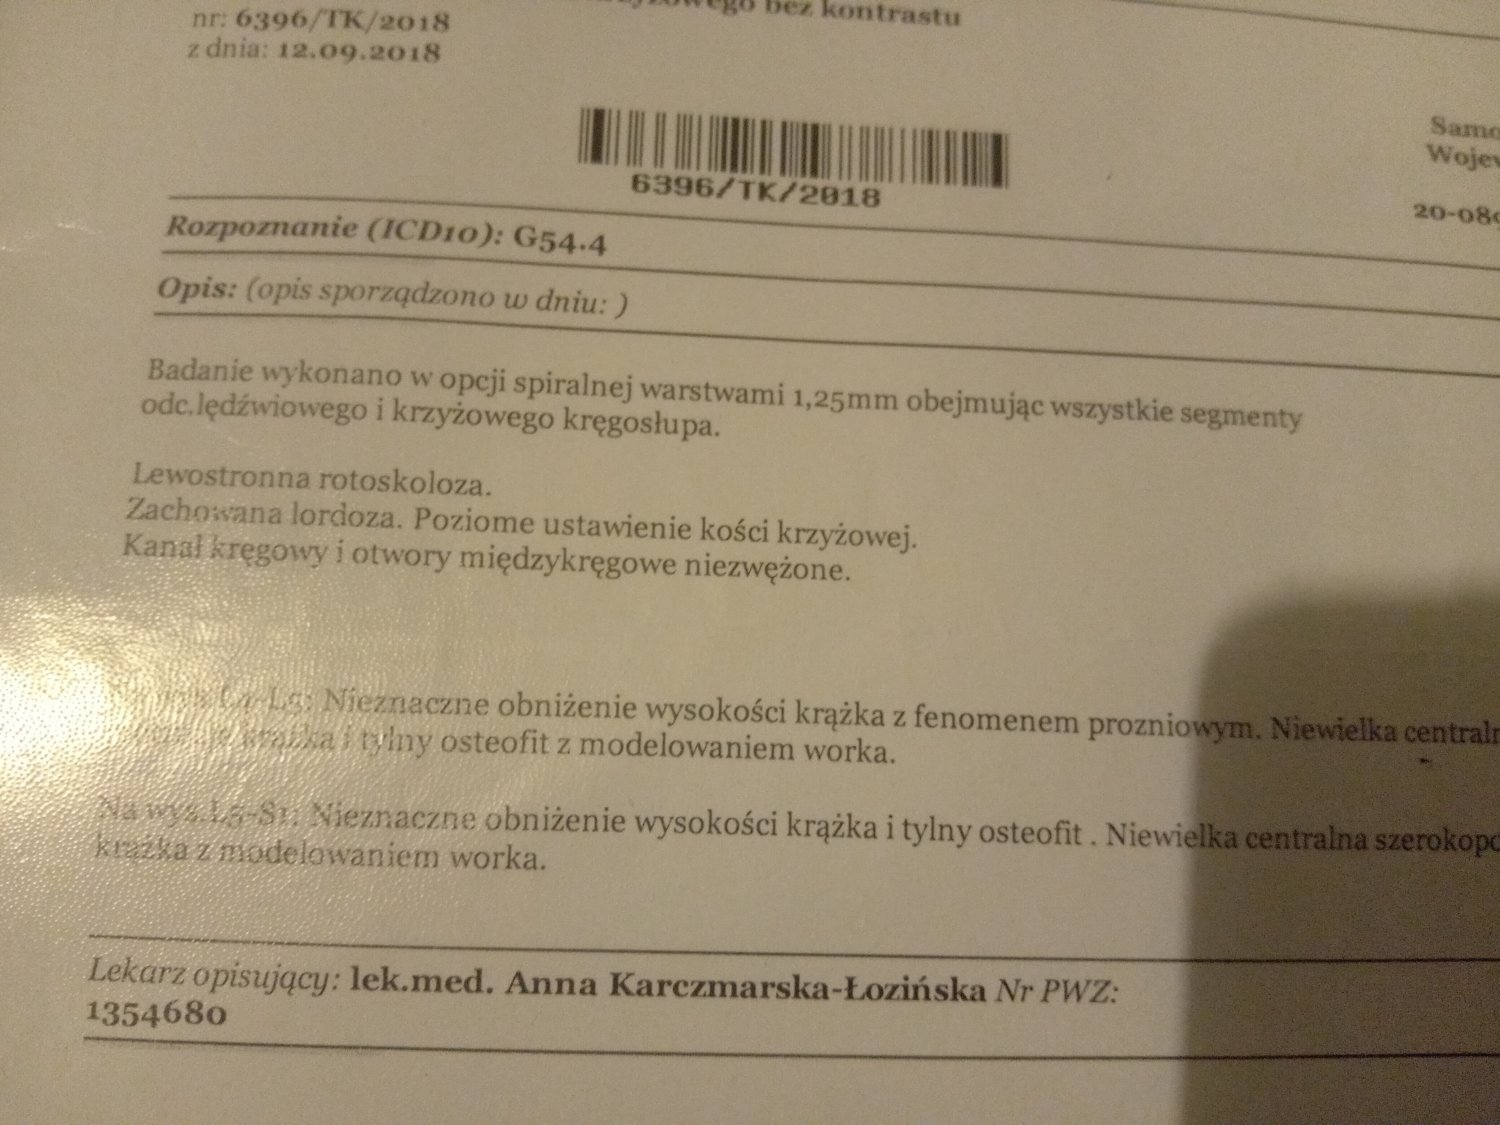

Witam jestem samotną matką wychowująca dwójkę dzieci . Spodziewam się córeczki jestem w 18 tygodniu ciąży moje problemy zaczęły się gdy miałam 18 lat i miałam wypadek samochodowy . Straciłam władzę w kręgosłupie ponieważ mam implanty w kręgosłupie piersiowym oraz przepuklinę krzyżowa. Dlatego też nie jestem wstanie pracować bo każdy wysiłek fizyczny to bardzo duży ból